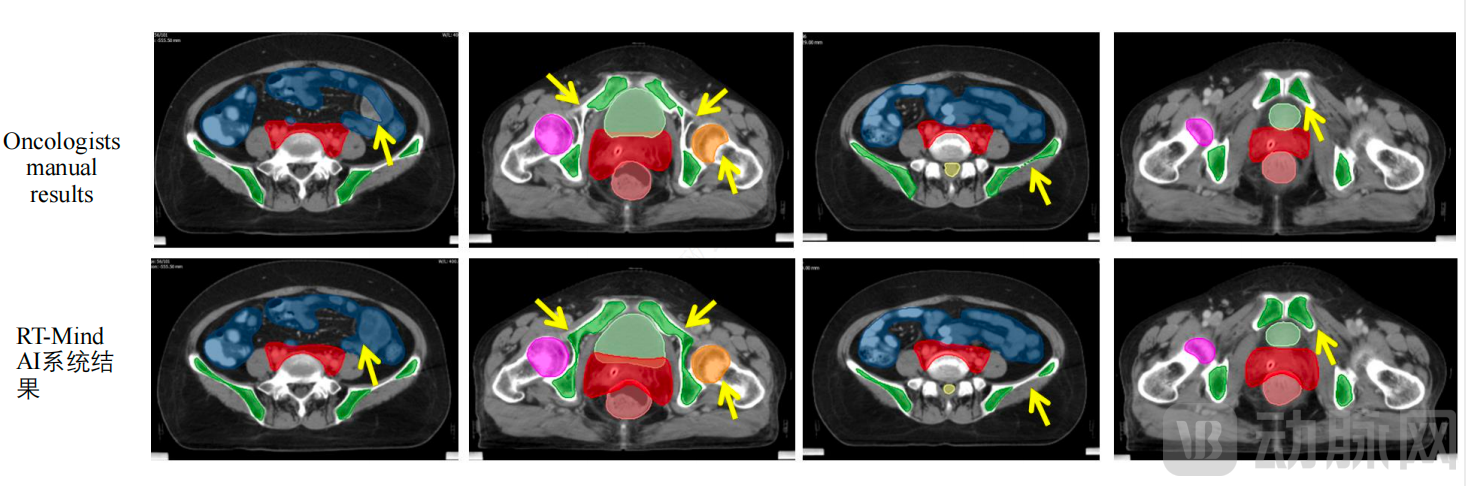

目前企业所推出核心产品“RT-Mind智能靶区勾画”以超过6万例高质量训练样本为基础,不仅可覆盖全身主要癌种,且可实现关键技术解决临床靶区(CTV)自动勾画。据悉,该准确度高达95%以上,勾画速度<10秒,全面兼容主流放疗系统,实现100倍效率提升(经多中心医院临床实测)。

回顾医智影一路走来,其从成立至今便始终聚焦“肿瘤精准治疗解决方案”打造。通过和清华大学以及包括北京协和医院、北京大学肿瘤医院、河南省肿瘤医院等全国顶级医院专家的合作,企业不断迭代与优化技术,为临床持续提供包括全自动勾画、功能丰富的放疗工作站,以及基于云平台的远程放疗系统等在内的,灵活且适应现有工作流程的多种产品组合,以真正实现用AI赋能放疗全流程,提高放疗科医生和物理师的工作效率。